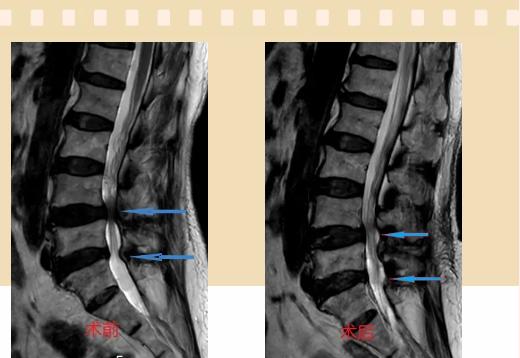

入院后李鵬副主任醫(yī)師為其進(jìn)行了詳細(xì)的查體,完善了術(shù)前的檢查,明確診斷為:腰椎管狹窄癥(L4/5、L5/S1),病人合并2型糖尿病,請內(nèi)分泌科會(huì)診,穩(wěn)定血糖后,麻醉科會(huì)診病人,排除手術(shù)禁忌,李鵬為病人制定了手術(shù)方案:單側(cè)入路雙側(cè)減壓(ULBD)。

手術(shù)采用三個(gè)微創(chuàng)小切口,兩個(gè)節(jié)段減壓手術(shù)時(shí)間2.5小時(shí),出血50ml。術(shù)后2天腰圍保護(hù)下床活動(dòng),術(shù)后5天順利出院。

傳統(tǒng)腰椎管狹窄癥的手術(shù)治療,往往需要切開減壓,同時(shí)需要內(nèi)固定融合術(shù),創(chuàng)傷很大,同時(shí)可能需要輸血,臥床時(shí)間較長,病人合并糖尿病,感染風(fēng)險(xiǎn)也高,而本次采用的UBE-ULBD手術(shù)切口更?。悠饋砑s3cm,如果是單節(jié)段狹窄只需要不到2cm切口)、創(chuàng)傷更小,術(shù)后恢復(fù)較快,可以更早地恢復(fù)正常活動(dòng)。

此外,手術(shù)保留了病變節(jié)段的穩(wěn)定性,是一種微創(chuàng)的椎管減壓手術(shù),能通過切除部分椎板、關(guān)節(jié)突關(guān)節(jié)、黃韌帶來解除神經(jīng)根和硬膜囊的壓迫,不需要額外行腰椎內(nèi)固定術(shù),不需要螺釘及融合器的植入,病人術(shù)后腰椎的活動(dòng)度不受影響。(盧   闖  劉   旭   袁錦鈺)